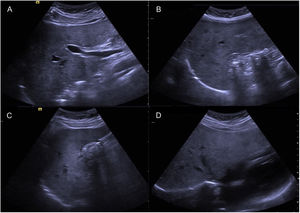

A 44-year-old woman began her illness with colicky epigastric pain that radiated to the right scapula, accompanied by nausea and vomiting. Her leukocyte count was 17,000 and bilirubin values were normal. She sought medical attention at the emergency room of a nonlocal hospital. A laparoscopic cholecystectomy was performed but there were intraoperative difficulties for identifying anatomic structures. The procedure was interrupted and a cholecystostomy tube was placed. She was referred to the Hospital General de México, where new radiologic studies and endoscopic retrograde cholangiopancreatography (ERCP) were carried out. A catheter was identified in the gallbladder, the intrahepatic bile duct was not dilated, and the common bile duct was regular, with a 4 mm diameter. Ultrasound imaging (Fig. 1A–D) and cholangiography through the cholecystostomy tube (Fig. 2A–D) showed a cystic gallbladder with stones, an unaltered intrahepatic bile duct located on the left, no evidence of biliary filling defects, and adequate passage of the contrast medium into the duodenum. The diagnosis of situs inversus was suspected and cholangioresonance imaging (Fig. 3A and B) was carried out, confirming the diagnosis. The study reported gallstones, the presence of a catheter in the gallbladder, and abdominal situs inversus totalis. Laparoscopic cholecystectomy was performed with no complications.